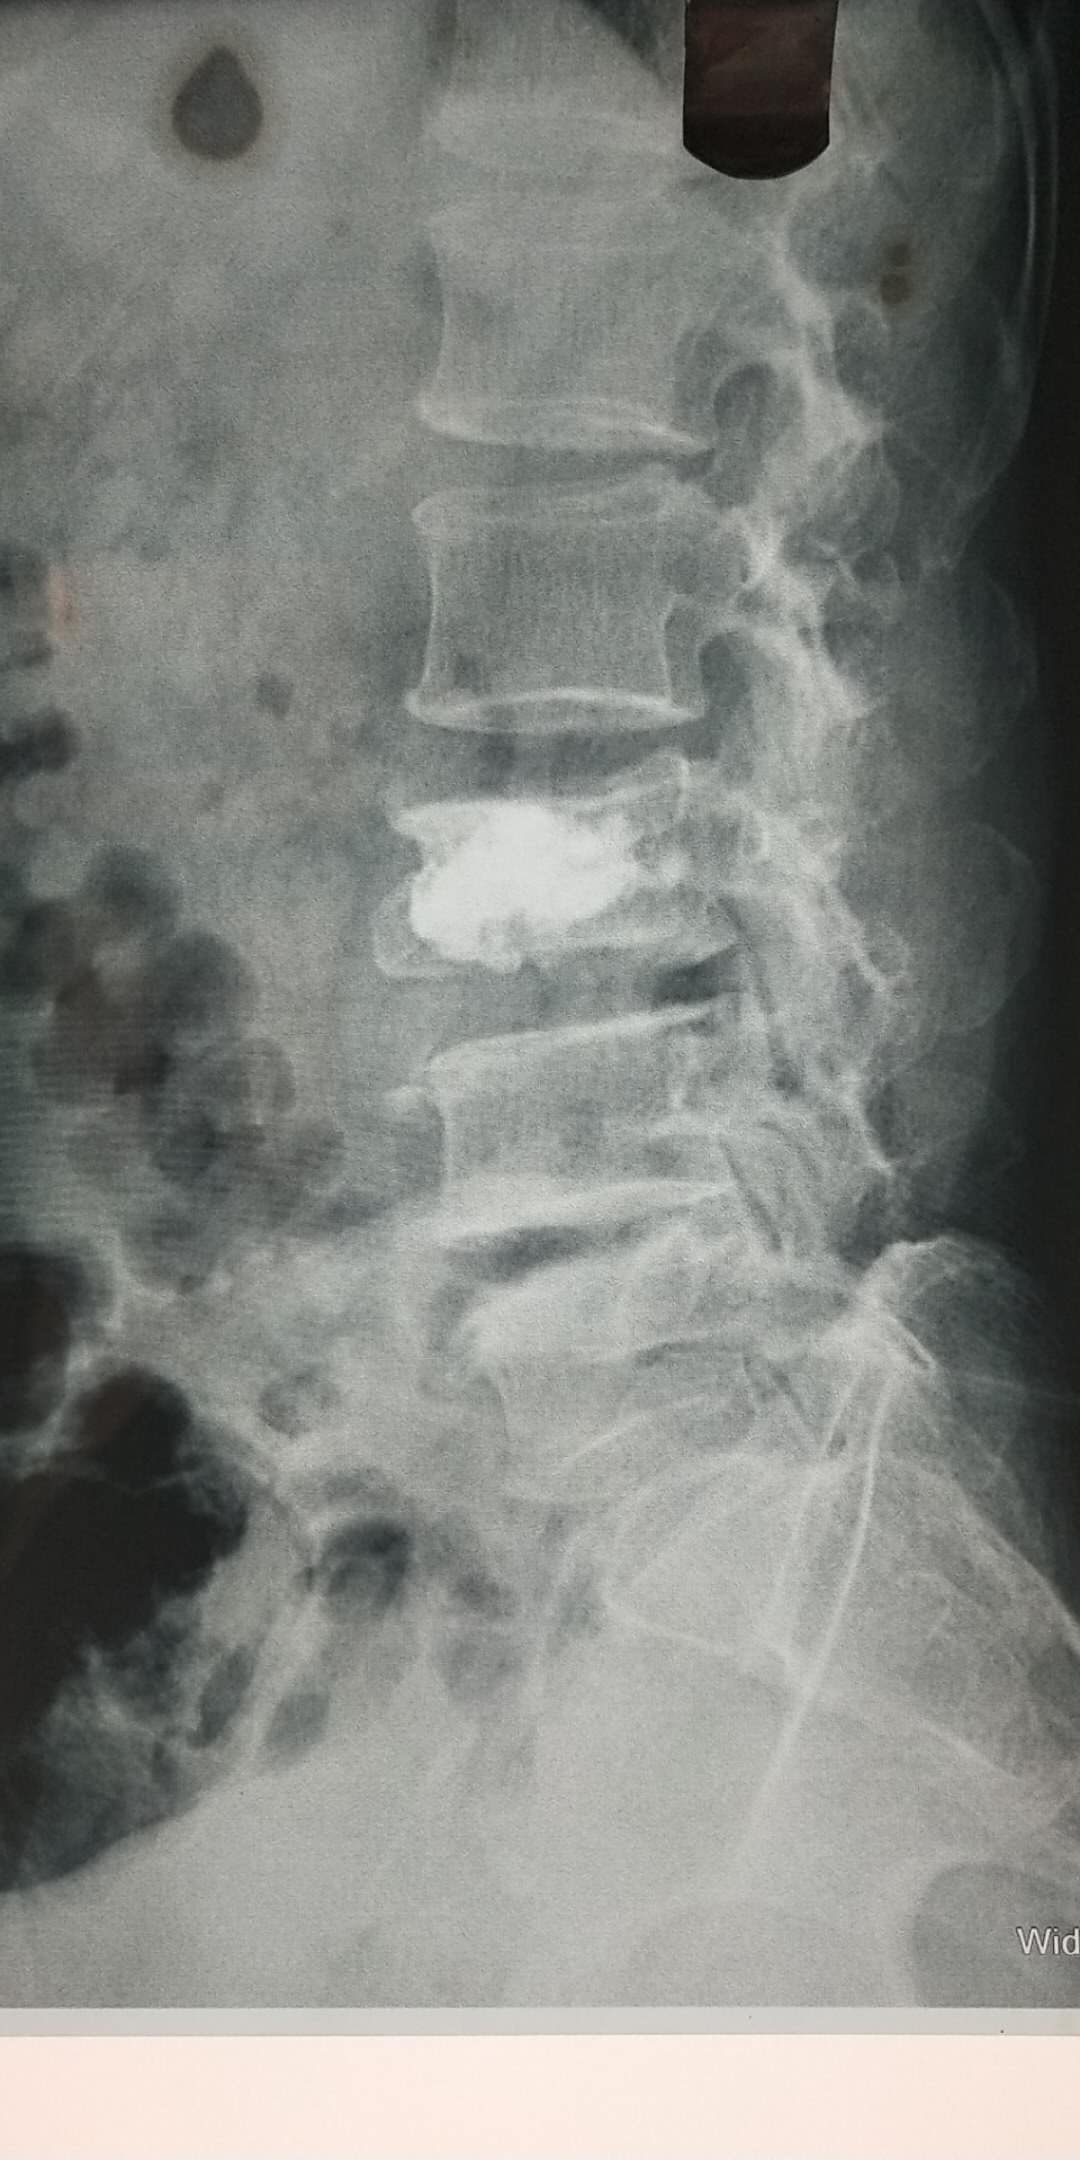

術(shù)后片子

骨一科已成功為數十名患者成功開(kāi)展PVP手術(shù)。僅今年3月份,在何光亮主任的帶領(lǐng)下,骨一科已經(jīng)成功開(kāi)展5例PVP手術(shù),術(shù)后患者相當滿(mǎn)意,全部患者術(shù)后可自行行走,擺脫臥床。3月21日患者王某,90歲,因摔傷致腰部疼痛3天為主訴入院,診斷腰1椎體骨折、骨質(zhì)疏松癥、高血壓等,住院后經(jīng)過(guò)科室術(shù)前討論,何主任為患者制定了PVP手術(shù)方案,于3月22日在行腰1椎體壓縮性骨折經(jīng)皮穿刺椎體成形骨水泥填充術(shù),術(shù)后24小時(shí)患者即下床活動(dòng),術(shù)后一周患者痊愈出院,隨訪(fǎng)患者已基本恢復到術(shù)前狀態(tài)。